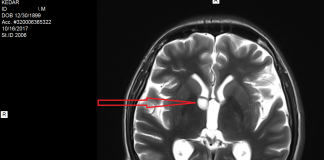

Afla in ce consta cancerul cerebral de la nivelul tesutului cerebral...

Cancerul cerebral primar este o forma rara de cancer care se formeaza in tesutul cerebral. Este intalnit mai mult la adultii de varsta medie...